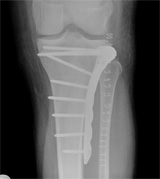

Fractures

FRACTURES (broken bones)      The skeleton is made to bear the load of all our activities. So when the bone is injured, it’s no surprise that activity often stops in the injured area. Proper healing of bones, especially around joints, with little tolerance for malpositioned surfaces, is crucial for return to normal. Our doctor  trained in one of the busiest trauma centers in Texas, and is well experienced in expert fracture care. He also realizes that recovery doesn’t just end with healing of the bone and will continue to guide you through the rehabilitation phase to help you truly recover from your injury.